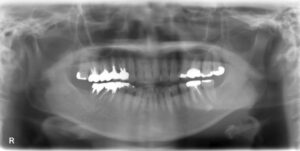

• 上下顎オールオン6症例

BEFORE AFTER 63歳男性/上顎6本・下顎6本 【治療内容】 全体的に歯が揺れてお食事がとりづらくなり、来院さ…